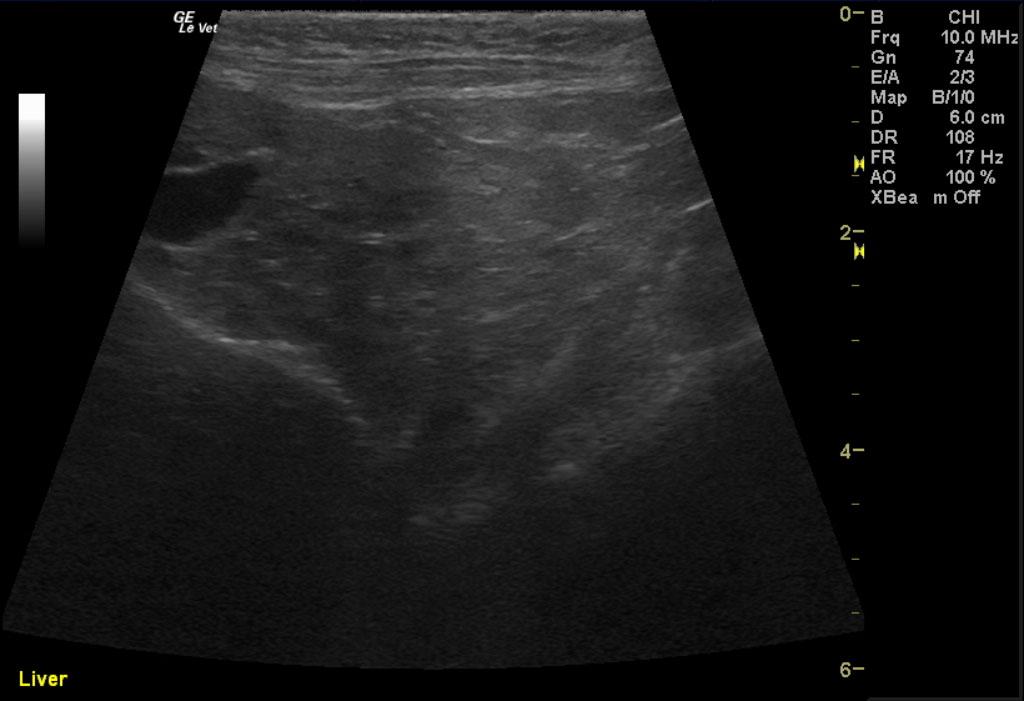

Image 1 & Video 1: The liver was moderately enlarged, rounded in shape having mildly hypoechoic echogenicity with multifocal hypoechoic and cystic nodules throughout. The gallbladder was normal in size, shape, and clean. Images 2-4 & Video 2-4: The left and right kidneys were severely enlarged with mild hydronephrosis in the right kidney. Both kidneys had hyperechoic cortices with large hypoechoic caps surrounding and invading the renal cortices (left kidney cap-7.4 mm in thickness, right kidney cap-13.6 mm in thickness). Image 5 & Video 5: Stomach: mucosal layer is mild/moderately thickened with overall wall thickness measuring 3.8 mm. Images 6: Intestine: there is focal mucosal layer thickening measuring up to 5.1 mm while the rest of the intestinal loops are of normal thickness. Video 6: Colon: the colonic wall appeared thickened at the ileocecolcolic junction. Image 7: Lymph Nodes: Multiple mesenteric lymph nodes were severely enlarged throughout the abdomen. The epigastric LN enlargement is shown in this image in the near field.